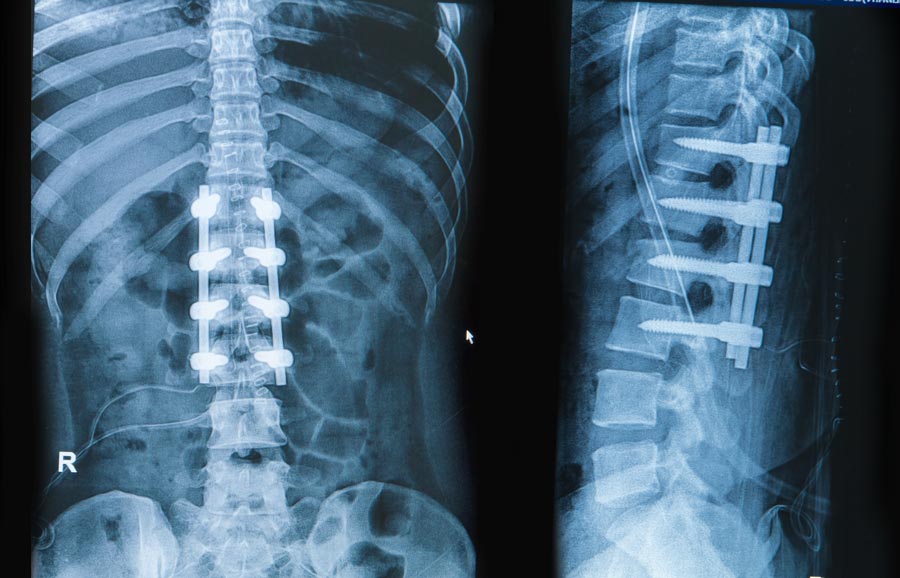

A spinal osteotomy is a surgical procedure used to correct certain deformities of spine. In this procedure, a section of the spinal bone is cut and removed for correction of spinal alignment. The spine osteotomy is also considered as a cosmetic surgery, especially in young patients to improve their cosmesis. Spine osteotomies can be broadly divided into three main types - posterior column osteotomy (PCO), the pedicle subtraction osteotomy (PSO) and vertebral column resection (VCR).

As the procedure requires a complete removal of bones, spinal fusion is also performed along with this procedure. It involves the use of a structural autograft, structural allograft or metal cage.